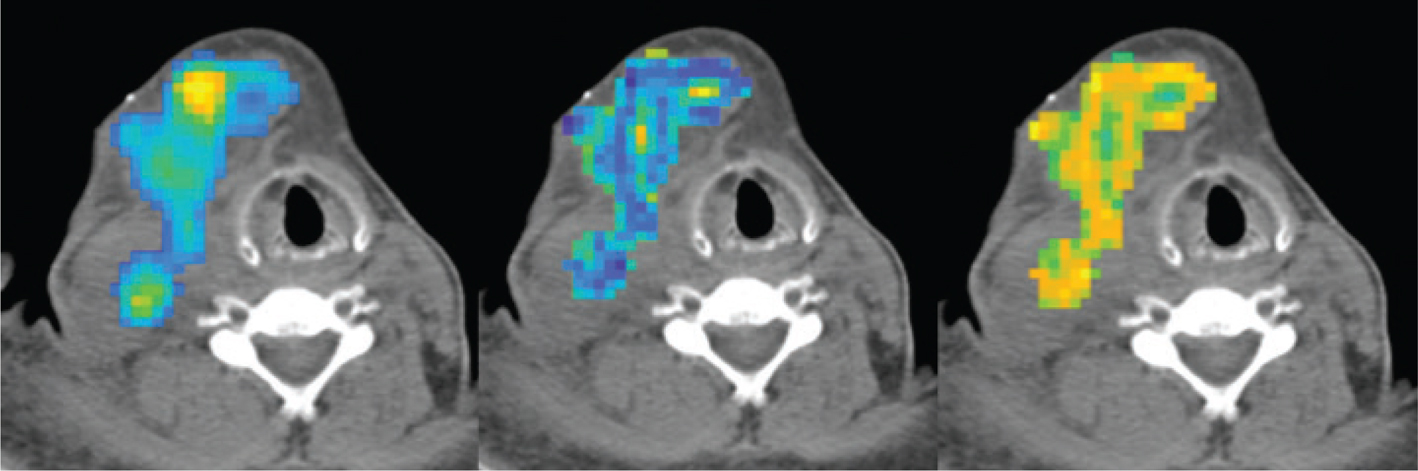

Fig 2

Figure 2. Example of different radiomics features (colored) over-imposed to the CT of a lymphomatous lesion in a DLBCL patient. SUV on the left, emphasis at the center and contrast to the right.